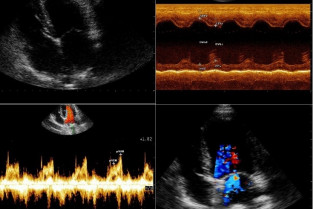

- d’effectuer de façon autonome une échocardiographie en réalisant sur des chiens, les principales coupes en mode BD et TM, et en faisant l’acquisition d’enregistrements Doppler ;

- de pratiquer l’échocardiographie dans les principales cardiopathies acquises et congénitales des Carnivores domestiques.